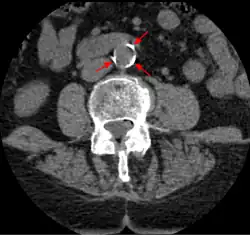

CT image of atherosclerosis of the abdominal aorta. A woman of 70 years old with hypertension and dyslipidemia.

The calcification deposits,[74] after they have become sufficiently advanced, are partially visible on coronary artery computed tomography or electron beam tomography (EBT) as rings of increased radiographic density, forming halos around the outer edges of the atheromatous plaques, within the artery wall. On CT, >130 units on the Hounsfield scale (some argue for 90 units) has been the radiographic density usually accepted as clearly representing tissue calcification within arteries. These deposits demonstrate unequivocal evidence of the disease, relatively advanced, even though the lumen of the artery is often still normal by angiography.

Examples of anatomical detection methods include coronary calcium scoring by CT, carotid IMT (intimal media thickness) measurement by ultrasound, and intravascular imaging techniques, such as intravascular ultrasound (IVUS), and intravascular optical coherence tomography (OCT),[85][86] allowing direct visualization of atherosclerotic plaques.